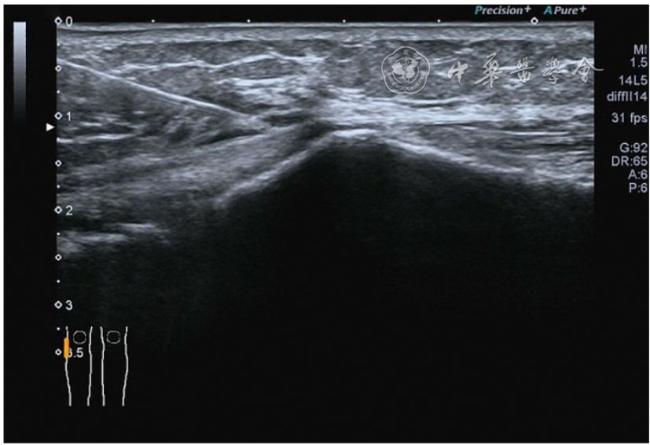

4.神经卡压液压松解加药物注射治疗。膝关节神经卡压主要涉及膝内上支、膝外上支、膝内下支、髌下支。可根据神经支配区域的临床检查确定卡压神经。临床上隐神经髌下支卡压常见。隐神经髌下支从隐神经发出后穿缝匠肌至膝内前下方,与深筋膜紧密相连(图24)。隐神经髌下支卡压出现膝关节内下侧酸痛、麻木,胫骨内侧髁压痛阳性,Tinel征阳性,局部皮肤痛觉减退。确定诊断后可行隐神经髌下支液压松解。患者平卧位,膝关节屈曲30°,下面垫一软枕。一般选用10 MHz以上超声探头,穿刺区域常规消毒,探头涂抹耦合剂后套入无菌手套碘伏消毒或使用无菌耦合剂。首先扫查神经短轴切面,确定神经后旋转为长轴切面引导注射。选用25G穿刺针头,抽吸0.5%利多卡因4 ml+地塞米松3 mg,从近端穿刺,沿神经表面纵轴方向,确定针尖在神经膜外后推注药物进行松解,注射完毕后拔出针头(图25),局部压迫2分钟,创可贴覆盖。

图25 超声引导下隐神经髌下支卡压液压松解加药物注射治疗